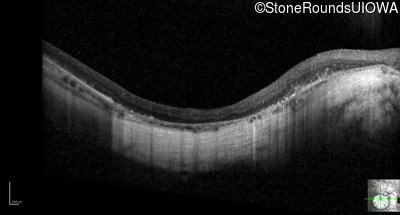

Optical Coherence Tomography - Left - 20/100 -1

Exemplar / OCT Stack

OCT Stack